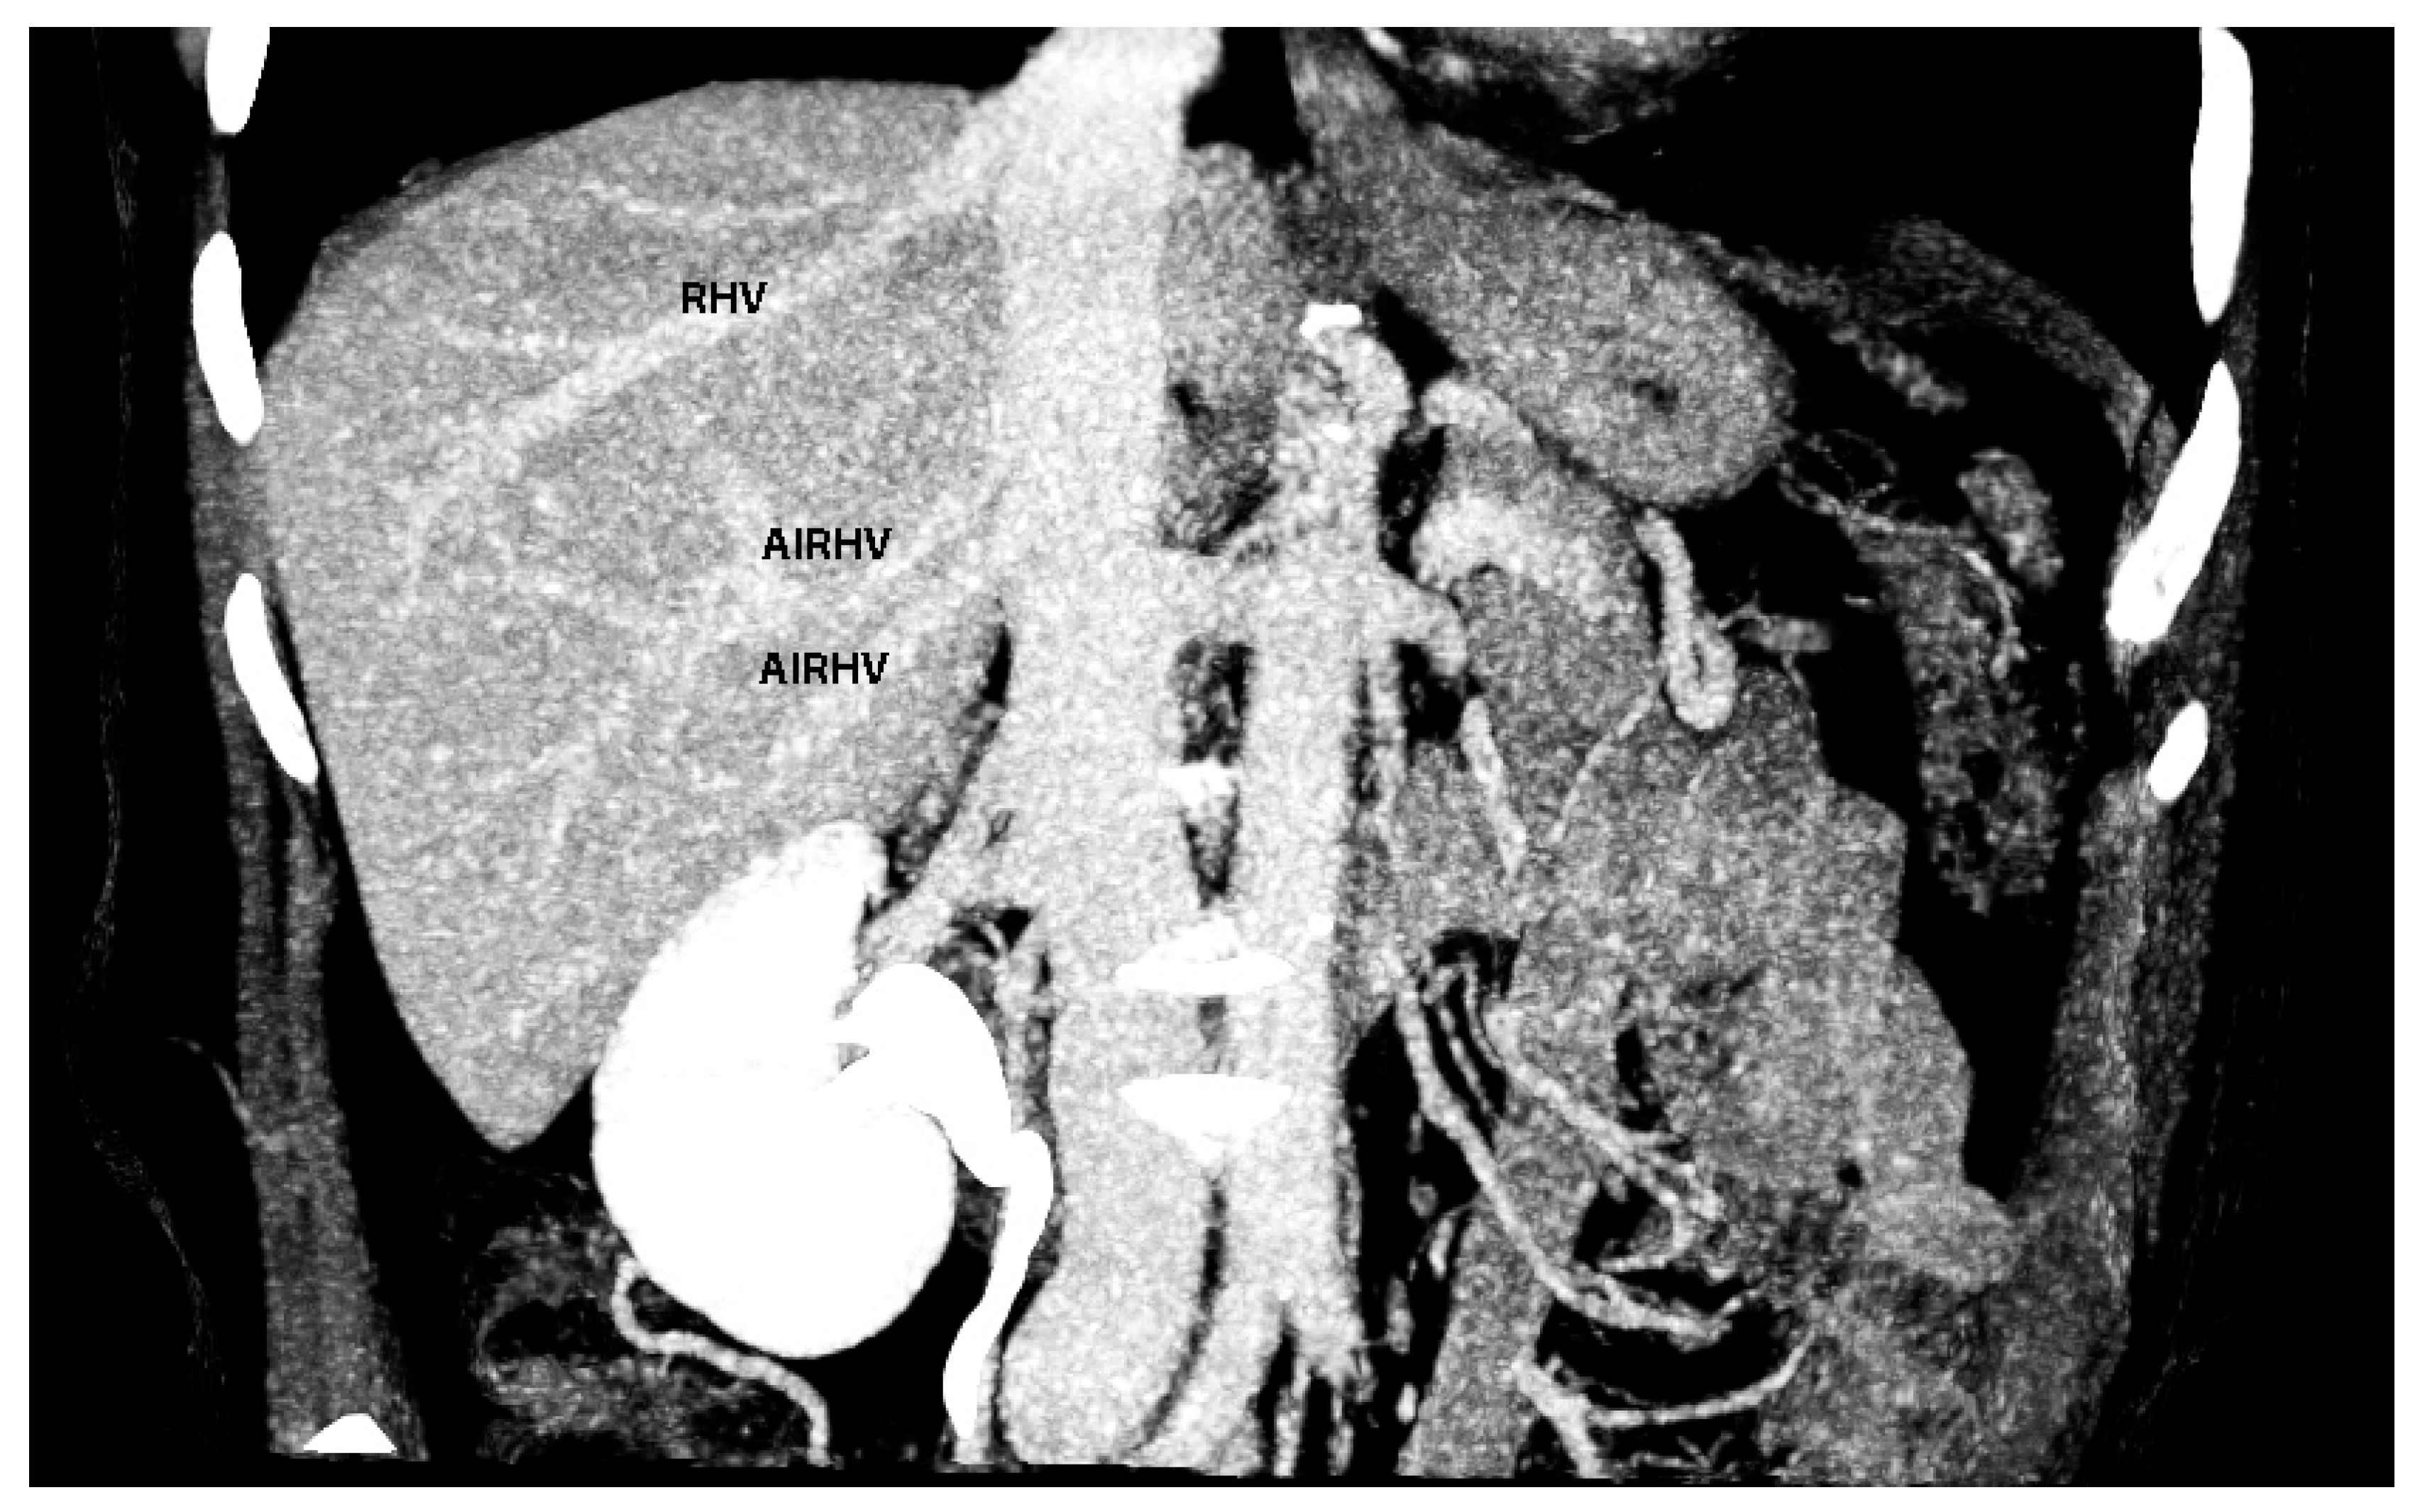

6.4. Hepatic Veins and IVC

7. Macroscopic and Microscopic Anatomy of the Liver—One Entity